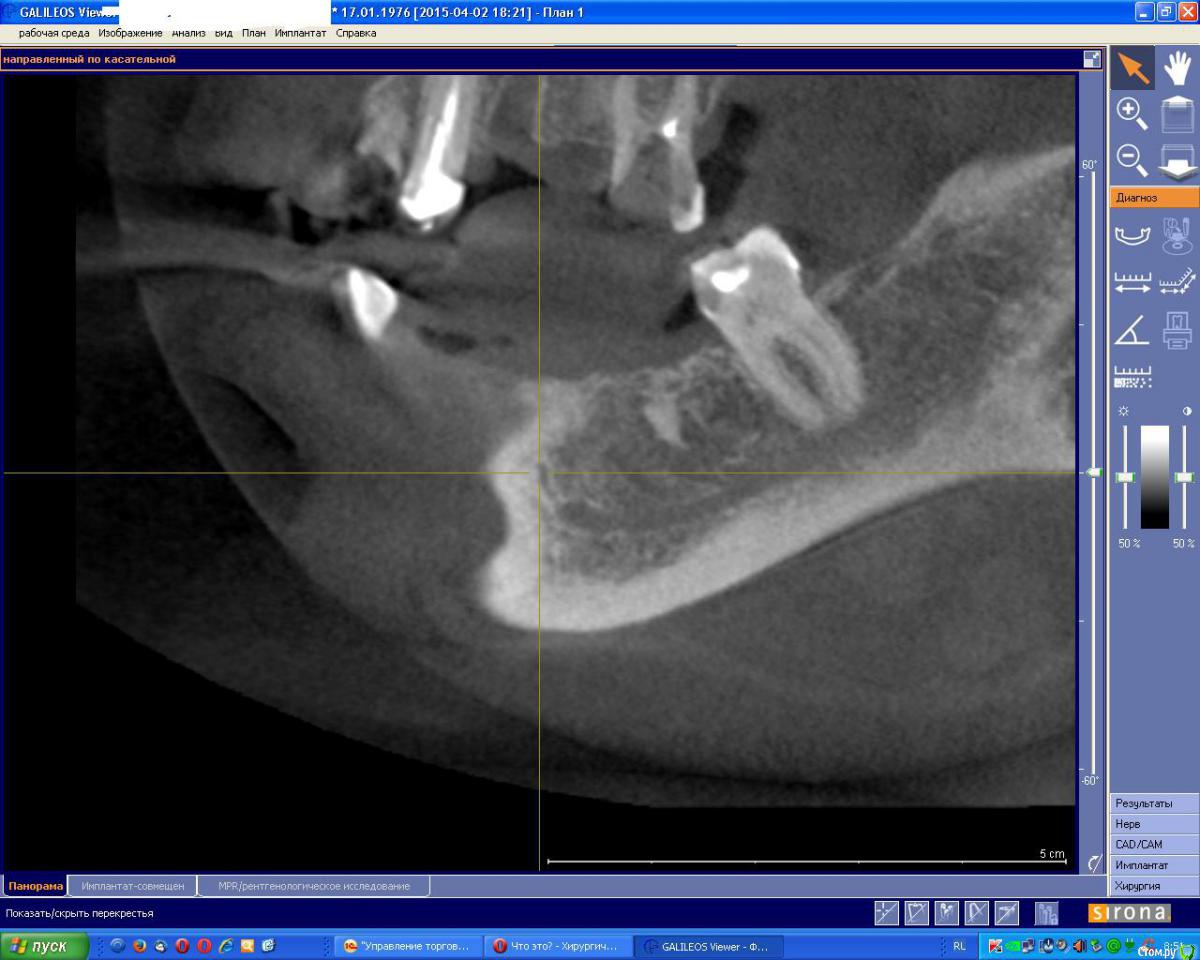

diesel87 Опубликовано 4 мая, 2015 Поделиться Опубликовано 4 мая, 2015 Посмотрите на него сбоку, его ход Ссылка на комментарий

an_ver Опубликовано 5 мая, 2015 Автор Поделиться Опубликовано 5 мая, 2015 Посмотрите на него сбоку, его ходВы правы.Ветка.Теперь вопрос:как мобилизоваться? Нагло срезать,и за счет основного ствола пойдет иннервация...или как Ссылка на комментарий

kriokov Опубликовано 5 мая, 2015 Поделиться Опубликовано 5 мая, 2015 Теперь вопрос:как мобилизоваться? скелетируйте не глубоко, думаю 7 мм у Вас есть чтоб не чикнуть. Если НКР не планируете то прокатит. Если планируете мобилизуйте лоскут как Mane показывал в ролике. Ссылка на комментарий

diesel87 Опубликовано 5 мая, 2015 Поделиться Опубликовано 5 мая, 2015 Вы правы.Ветка.Теперь вопрос:как мобилизоваться? Нагло срезать,и за счет основного ствола пойдет иннервация...или какТам корень моляра? Ссылка на комментарий

an_ver Опубликовано 6 мая, 2015 Автор Поделиться Опубликовано 6 мая, 2015 Там корень моляра?Да,кто то забыл Ссылка на комментарий